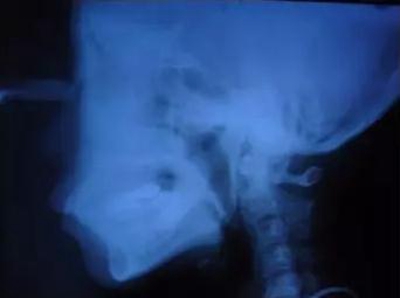

▲ 圖2 典型病例矯治前,患者牙(牙合)像、曲面斷層、頭顱側(cè)位片及側(cè)面像